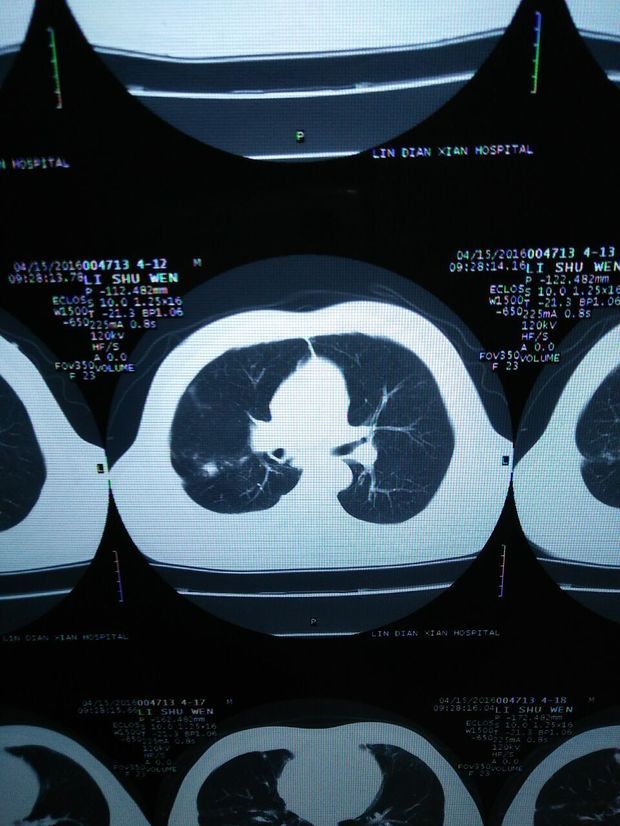

肺门肿瘤

肺门肿瘤,肺部肿瘤

右侧肺门区肿瘤.

肺部肿瘤

肺门ct